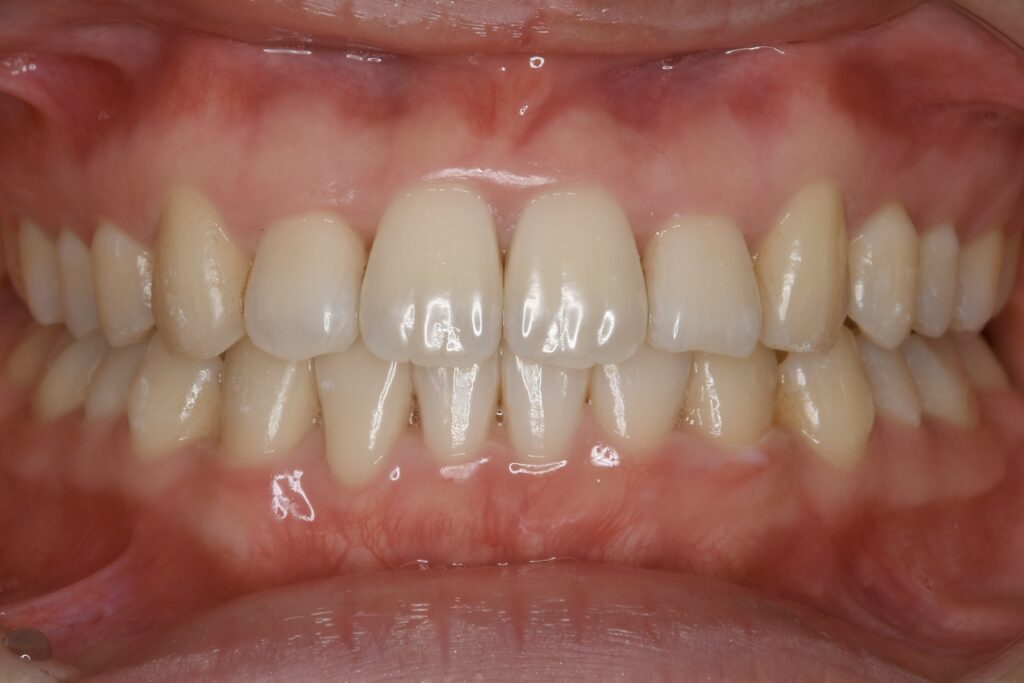

AFTER

上下とも歯並びの横幅を広げながら、でこぼこを解消しました。

マウスピース矯正(インビザライン)

治療期間

1年1ヶ月

10回

85万円程度(税別)